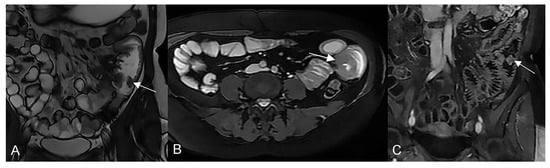

Transmural involvement can develop a sinus tract that reaches the serosa resulting in a fistula’s channel that connects different structures (e.g., entero-enteric, entero-vesical, and entero-vaginal fistula). In fact, sinus passages are closed off from perforations that result in phlegmons or, if infected, abscesses, but do not affect the nearby organs or the skin (Figure 7 and Figure 8).

The sinus tracts that represent a sealed-off perforation that develops into a phlegmon or, if infected, into an abscess (9) but does not reach adjacent organs or the skin. Therefore, they end up blind.

Figure 8.

Coronal (A–C) contrast-enhanced fat-suppressed T1-weighted images of the same patient show the sinus tracts that represent a sealed-off perforation that develops into a phlegmon or, if infected, into an abscess (9) but does not reach adjacent organs or the skin. Therefore, they end up blind.

Unlike the sinus tracts, a fistula is defined as a pathologic channel connecting two or more epithelialized surfaces [11]. Fistulae can be simple (single extra enteric tract: enter enteric, enter colic, enter vesical, enterocutaneous, or rectovaginal) or complex (branching and intersecting fistulas, sometimes with a star-like appearance [5]). They represent a complication in approximately 14–50% of the patients with Crohn’s disease (Figure 9, Figure 10 and Figure 11).

Figure 9.

Pathological junctions of intestinal segments through enteroenteric fistulas, which represents internal fistulas that connect intestinal segments such as ileo-sigmoidal (A) and ileo-colic (B).

Figure 10.

Axial (A) and coronal (B,C) contrast-enhanced fat-suppressed T1-weighted images and axial FIESTA image (E) of the same patient show a complex fistula formed by the intersection of multiple fistulous arms that connect pathological segments of the small intestine to each other and to the ascending colon through the mesentery. These fistulous pathways, intersecting each other, end up taking on the starry appearance, typical of complex fistulas (D).